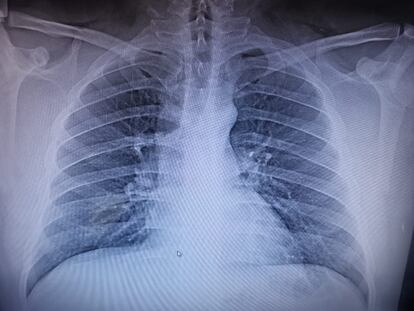

Tres días más tarde, la situación de Jorge ha empeorado: ha tenido más de 38 grados de temperatura, ha perdido el olfato, le duelen los músculos. “El doctor del triaje respiratorio considera que no cumple los criterios para covid. No tenía fiebre en ese momento porque había tomado paracetamol en casa”, se queja su pareja, Yuriko Montaño. Le mandan una placa torácica y una prueba PCR, que debe hacerse en otro hospital, en Las Américas.“Le dijeron que no se veía tan mal”, añade una compañera, y llora.

Llegó la Navidad, la jefa de Gobierno de Ciudad de México, Claudia Sheinbaum, advertía contra las fiestas, las posadas, suplicaba quedarse en casa. En este departamento de la Gustavo Madero fue un día corriente en la rutina de la enfermedad. Cenaron caldo de pollo, Jorge quiso ver la misa, se acostaron temprano. Pronto, la fiebre desapareció. “Pero el daño pulmonar ya estaba hecho. Si se quitaba el oxígeno, desaturaba hasta el 45%. A mí me asustaba, es la mejoría de la que hablan antes de... la mejoría que no quieres”, dice quebrada su novia. “Él decía que no se quería morir, siempre fue muy positivo, pero sí hizo hincapié, que él no, que él no”, cuenta su hermana.